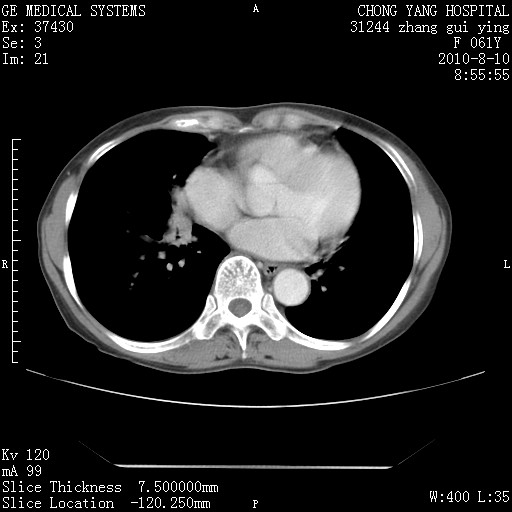

1、支持考虑右侧中央型肺癌伴右肺中叶节段性不张及下叶支气管黏液痰栓    2、左肺上叶舌段感染。

确切的说:1:右肺下叶中心型肺癌侵及中叶支气管并中叶不张,纵膈淋巴结转移。2:左肺舌叶炎症。3:右侧胸腔少量积液

块影平扫32hu,动静脉期62-70hu.

1:右肺下叶中心型肺癌侵及中叶支气管并中叶不张,纵膈淋巴结转移。2:左肺舌叶炎症。3:右侧胸腔少量积液。支持!

右肺下叶中心型肺癌侵及中叶支气管并中叶不张,纵膈淋巴结转移。2:左肺舌叶炎症。3:右侧胸腔少量积液